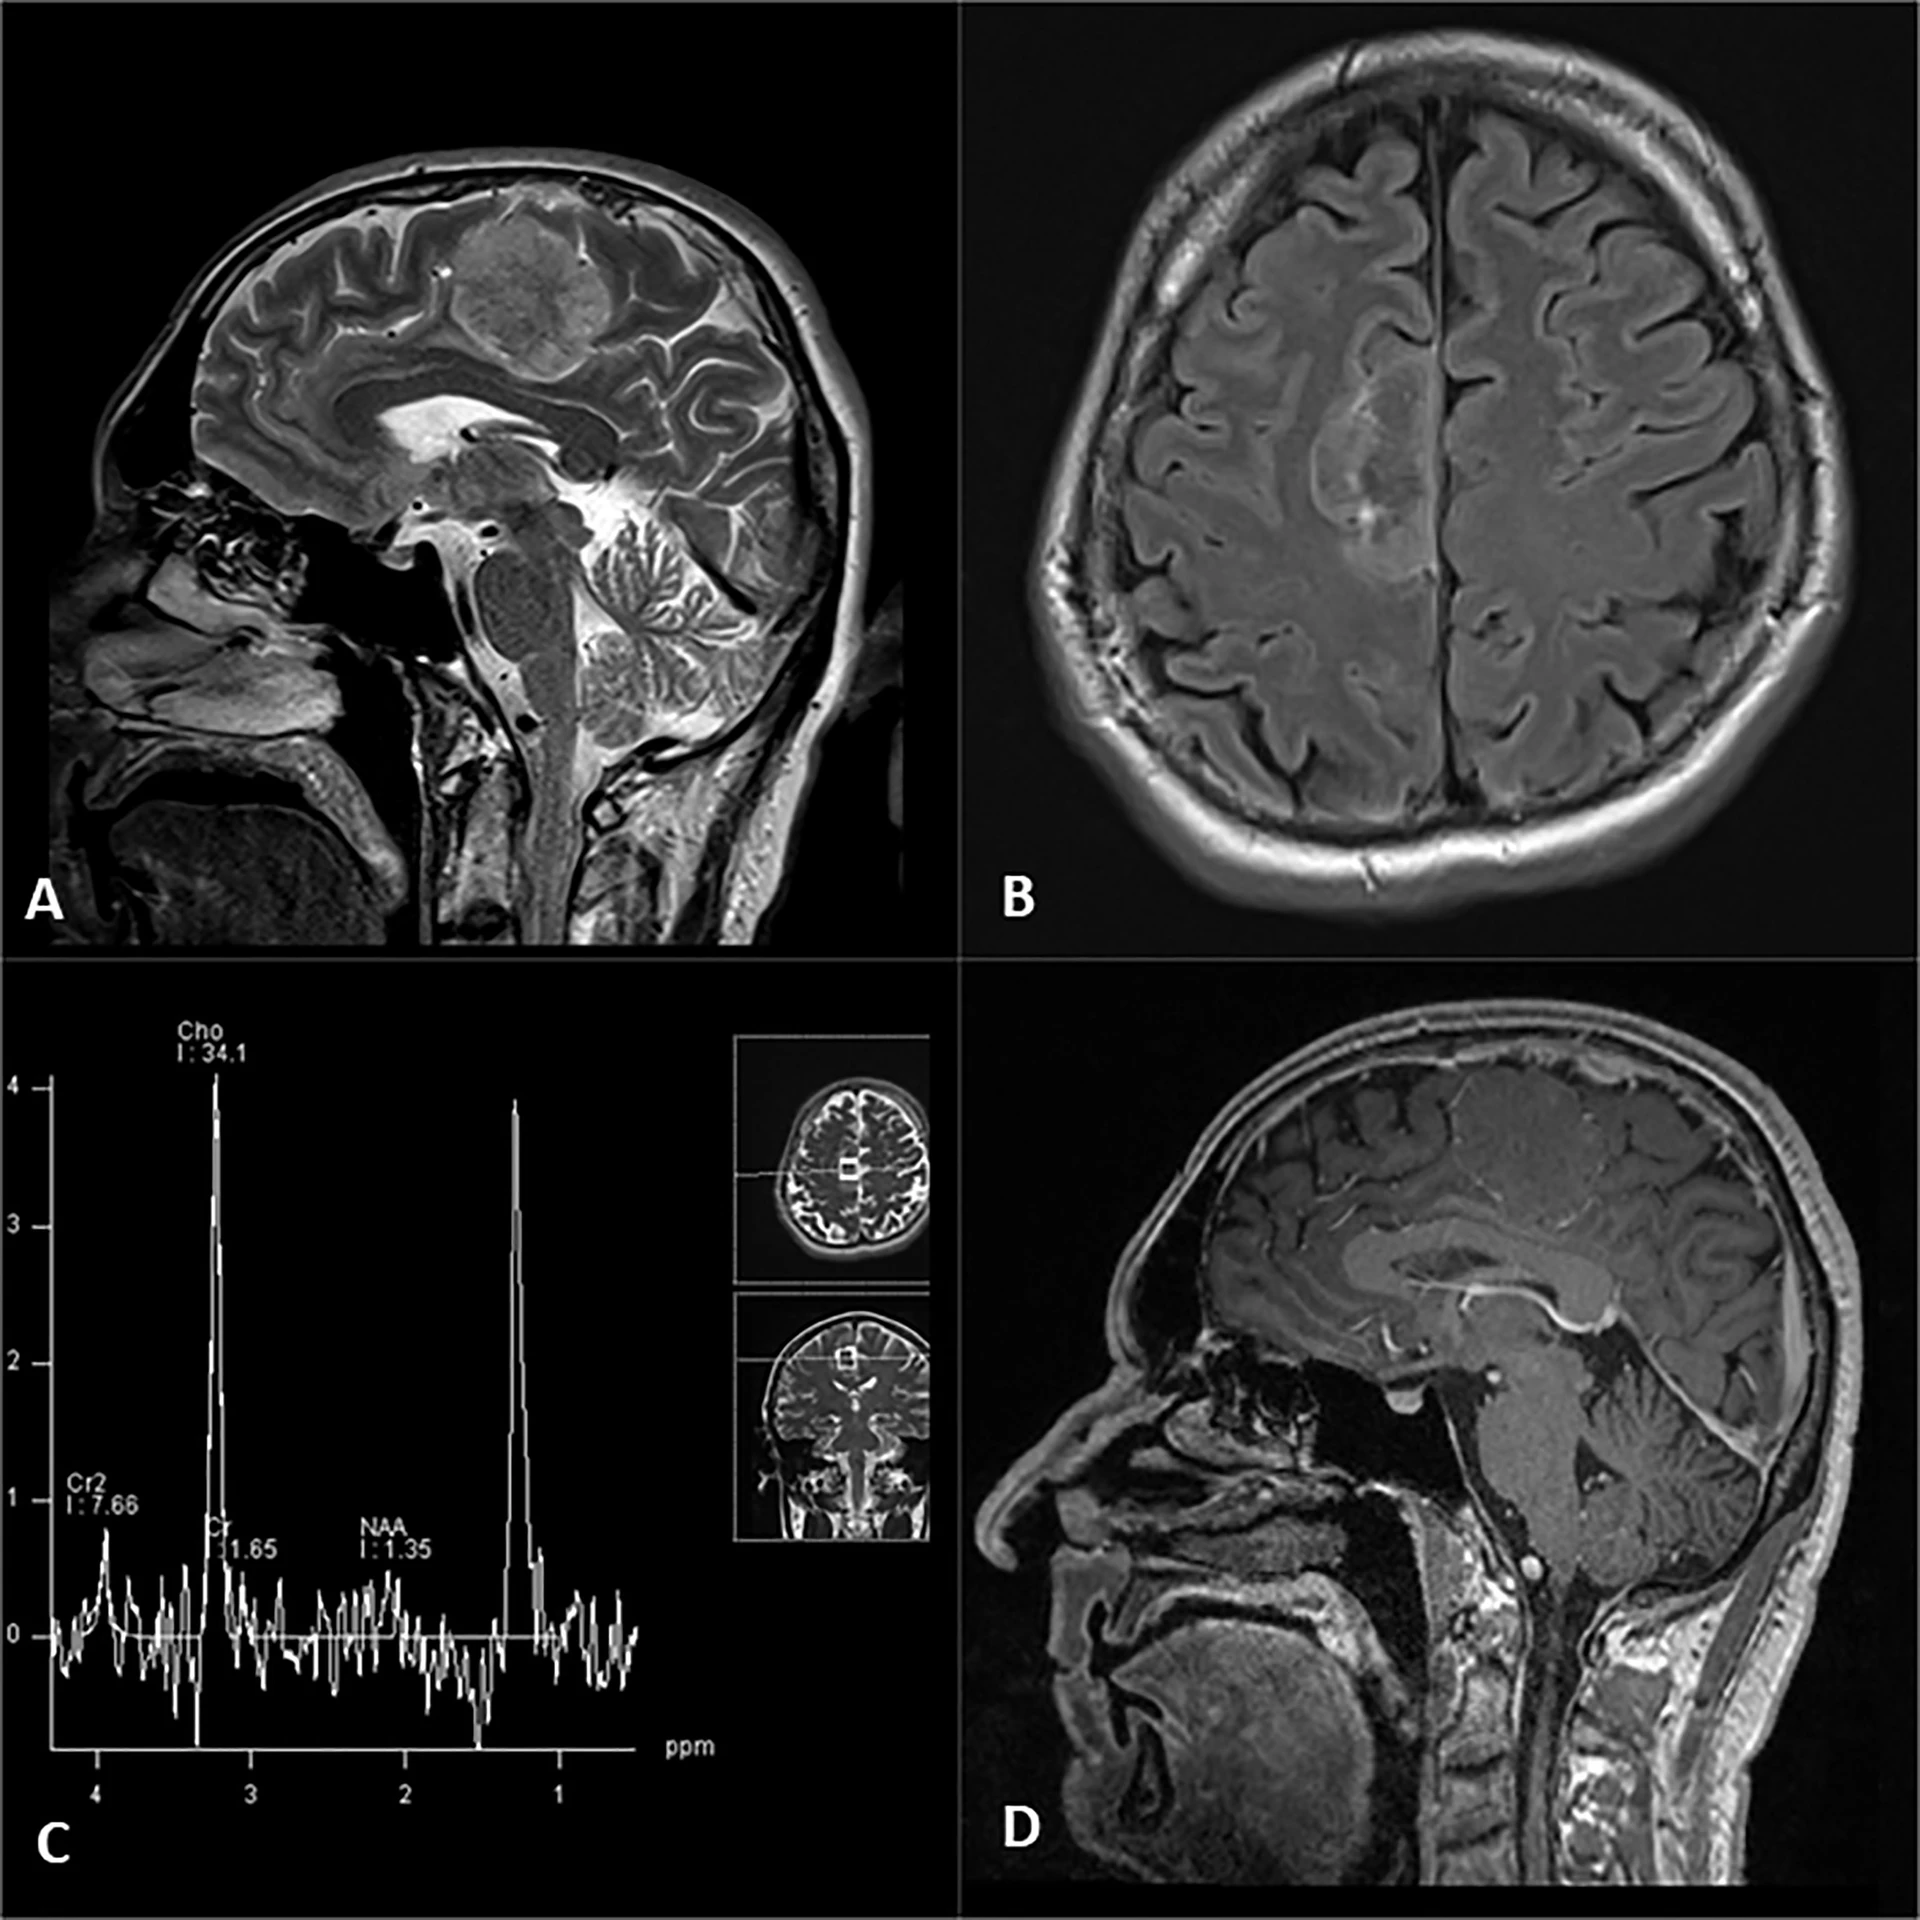

- تصویربرداری از مغز: دقیقترین روش برای تشخیص تومورهای مغزی MRI است. این نوع تصویربرداری میتواند اندازه، شکل و محل تومور را به وضوح نشان دهد. علاوه بر MRI سی تی اسکن نیز یکی دیگر از روشهای تصویربرداری از مغز است. سی تی اسکن به تشخیص تومورهای مغزی کمک کند، اما دقت آن به اندازه MRI نیست.